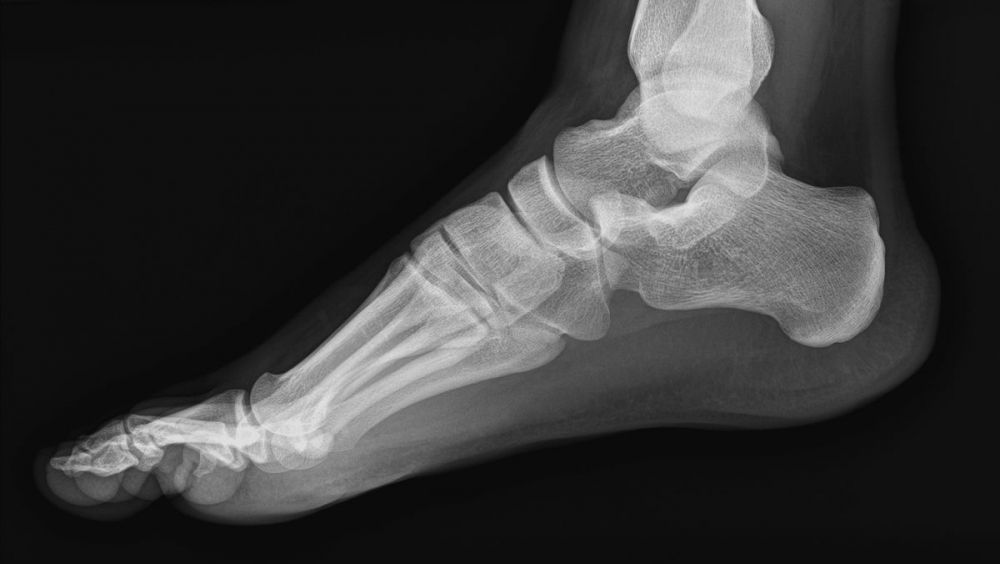

Pero, ¿cuándo se hacen radiografías? Estas pueden servir para detectar muchos tipos de enfermedades o anomalías de nuestro organismo. Aparte del uso que se hace para detectar caries o problemas en los dientes, los usos más comunes son a la hora de detectar una fractura en un hueso.

También, gracias al uso de estas, se detectan lesiones fuera de las fracturas y anormalidades en las articulaciones. Otras prácticas específicas mediante el uso de radiografías son las que se realizan en la columna, en el tórax, en el pecho de las mujeres (mamografía), o los llamados TAC en la cabeza, columna, y abdomen y pelvis.